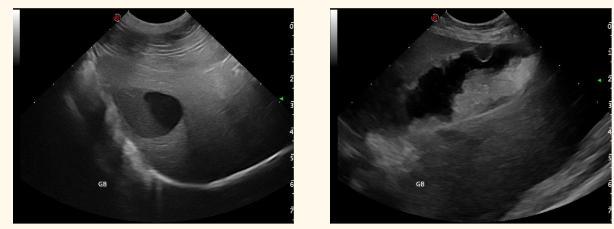

what are these 3 common findings in the urincary bladder